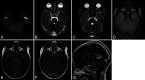

Observations: The authors present a case of a 14-month-old child who presented with fever and a first-time seizure. Computed tomography of the head suggested an epidural abscess; however, magnetic resonance imaging characteristics of the lesion were consistent with torcular pseudomass, a normal variant. At the 3-month follow-up, the child was continuing to do well and had not had another seizure. There have been no indications for surgical intervention or additional radiographic surveillance.

Lessons: The differential diagnosis for torcular pseudomass includes dural venous sinus thrombosis, dermoid cysts, occipital encephalocele, eosinophilic granuloma, and primary and metastatic tumors, such as neuroblastoma. The management of each of these disorders in the differential diagnosis may be much more invasive than continued observation in the case of torcular pseudomass. Therefore, it is important for pediatric neurosurgeons to become familiar with this developmental anomaly of the dura and occipital skull.